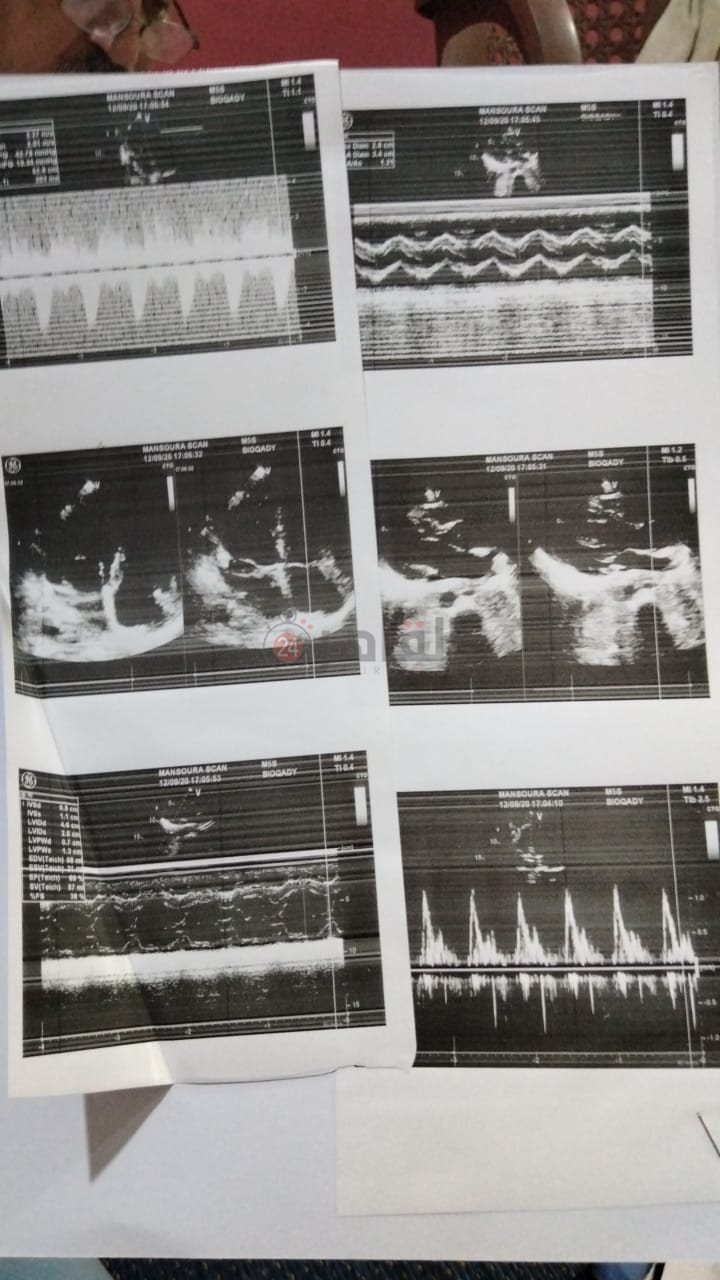

كما أكدت أنه تم التواصل مع أحد الأطباء المتخصصين في البطني الذي أكد إصابتها بوحمتين في الأمعاء الدقيقة وضرورة تدخل جراحي لإزالتها وتم التواصل مع طيب جراحة واعطاها كبسوله لتصوير الجهاز الهضمي وتبين أن جزء من الأمعاء دايب وخلال إجراء عملية جراحية كبيرة لإزالة الأمعاء الدايبة تبين أن جميع أمعاء المعدة دايبة وملتصقة ببعضها البعض ولم يستطع طبيب الجراحة إجراء العملية وقدرت تكاليفها 70 ألف جنيه وتطور الأمر إلى إصابتها بنزيف مستمر.

أضافت شقيقة تبارك أيضا: مسكتناش وبقينا نلف بأختي وتم عرضها على عدة أطباء بين بطني ونساء وولادة وأورام وأصبح وزنها يتناقص إلى أن بلغ 40 كيلو، وتوصل الأطباء إلى أنها مصابة بمرض نادر ويستحيل علاجها إلا في ألمانيا.